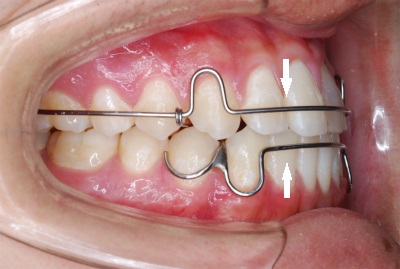

理想のリテーナーがないのであれば新たに作ってしまおうと試行錯誤を重ねて、先日ようやく納得のいく形に仕上がりました。

今回作り上げたリテーナーは見た目にも非常に優れており、プレートタイプとクリアリテーナーのいいとこどりをしたともいえます。

画像のタイプは一例で、他にもバリエーションがあります。弾性を持つ透明の樹脂ワイヤーは見た目と機能だけではなく生体適合性にも非常に優れた医用高分子材料を使用しております。

他のリテーナーにはない一番の特徴は 表側・裏側ともに弾性機能を持つ樹脂ワイヤーで覆うことで歯の後戻りに対する動きを抑えていること です。

また、この見た目と機能に優れたリテーナーを裏側矯正治療をされた方々にもお見せしたところ、”これなら目立たないし快適そうなのでぜひ作って欲しい” という感想をいただきました。

透明のワイヤーは歯の色と同化してイイ感じですよ